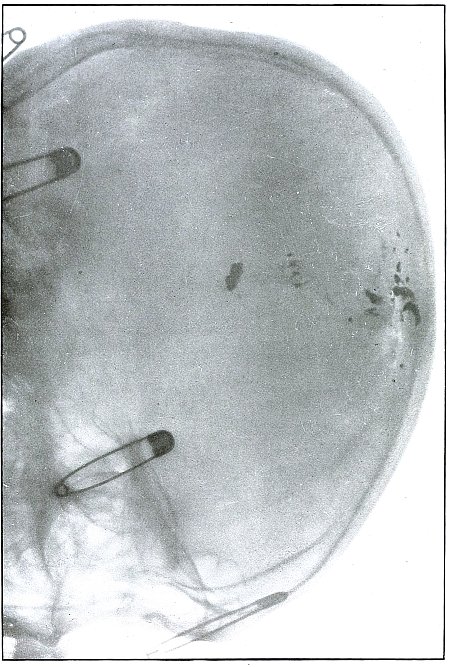

Plate 52.

[Pg 115]

Rifle—Plate 52.

LOWER EXTREMITY.

Gunshot Fracture of the Upper Shaft of the Femur.

The course of the bullet was anteroposterior and pierced the axis

of the shaft of the femur with three radiating lines of fracture,

resulting from the perforating action of the bullet striking the bone

at long range and with greatly reduced energy.

This plate shows the lateral separation of large fragments,

which is typical of gunshot wounds of long range.

Such wounds are usually not infected.

Emergency treatment is antiseptic dressing and coaptation with

extension and temporary splint, so that it may support the bone for

transportation and may be easily removable at place of continued

treatment.

In these cases with lateral separation of fragments, it is imperative

to supplement extension with pressure in a line perpendicular to the

long axis of the femur.

[Pg 116]